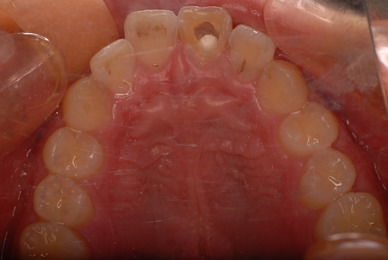

現実を見ればお口の中には“異物”である金歯、銀歯、セラミック、インプラントのオンパレードです。

これ等のものは、異物です。無い方が病気にならず健康でいられるのです。

“お口の中から差し歯、入れ歯、詰め物を追放しましょう。”

お口の中から差し歯、入れ歯、詰め物を追放しましょう!